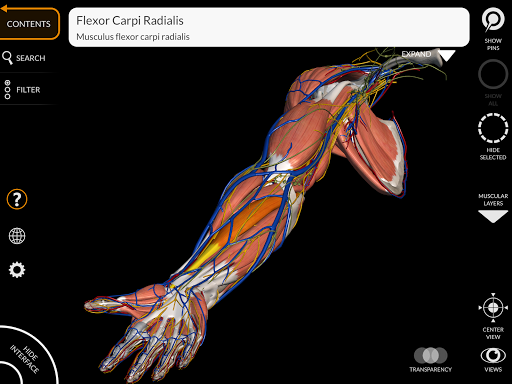

"Anatomy 3D Atlas" memungkinkan Anda mempelajari anatomi manusia dengan cara yang mudah dan interaktif.

Melalui antarmuka yang sederhana dan intuitif, Anda dapat mengamati setiap struktur anatomi dari sudut mana pun.

Model 3D anatomi sangat terperinci dan memiliki tekstur hingga resolusi 4k.

MODEL ANATOMI 3D

• Sistem muskuloskeletal

saraf • Sistem pernapasan • Sistem pencernaan • Sistem urogenital (pria dan wanita) • Sistem endokrin • Sistem limfatik • Sistem mata dan telinga FITUR • Antarmuka yang sederhana dan intuitif • Putar dan perbesar setiap model dalam ruang 3D • Opsi untuk menyembunyikan atau mengisolasi satu atau beberapa model yang dipilih • Filter untuk menyembunyikan atau menampilkan setiap sistem • Fungsi pencarian untuk menemukan setiap bagian anatomi dengan mudah • Fungsi penanda untuk menyimpan tampilan khusus • Rotasi cerdas yang menggerakkan pusat rotasi secara otomatis • Fungsi transparansi • Visualisasi otot melalui tingkat lapisan dari yang superfisial hingga yang terdalam • Dengan memilih model atau pin, istilah anatomi terkait akan muncul • Deskripsi otot: asal, • Tampilkan/ Sembunyikan antarmuka UI (sangat berguna dengan layar kecil) MULTIBAHASA • Istilah anatomi dan antarmuka pengguna tersedia dalam 11 bahasa: Latin, Inggris, Prancis, Jerman, Italia, Portugis, Turki, Rusia, Spanyol, Mandarin, Jepang, dan Korea • Istilah anatomi dapat ditampilkan dalam dua bahasa secara bersamaan PERSYARATAN SISTEM • Android 8.0 atau yang lebih baru, perangkat dengan RAM minimal 3GB Reversi